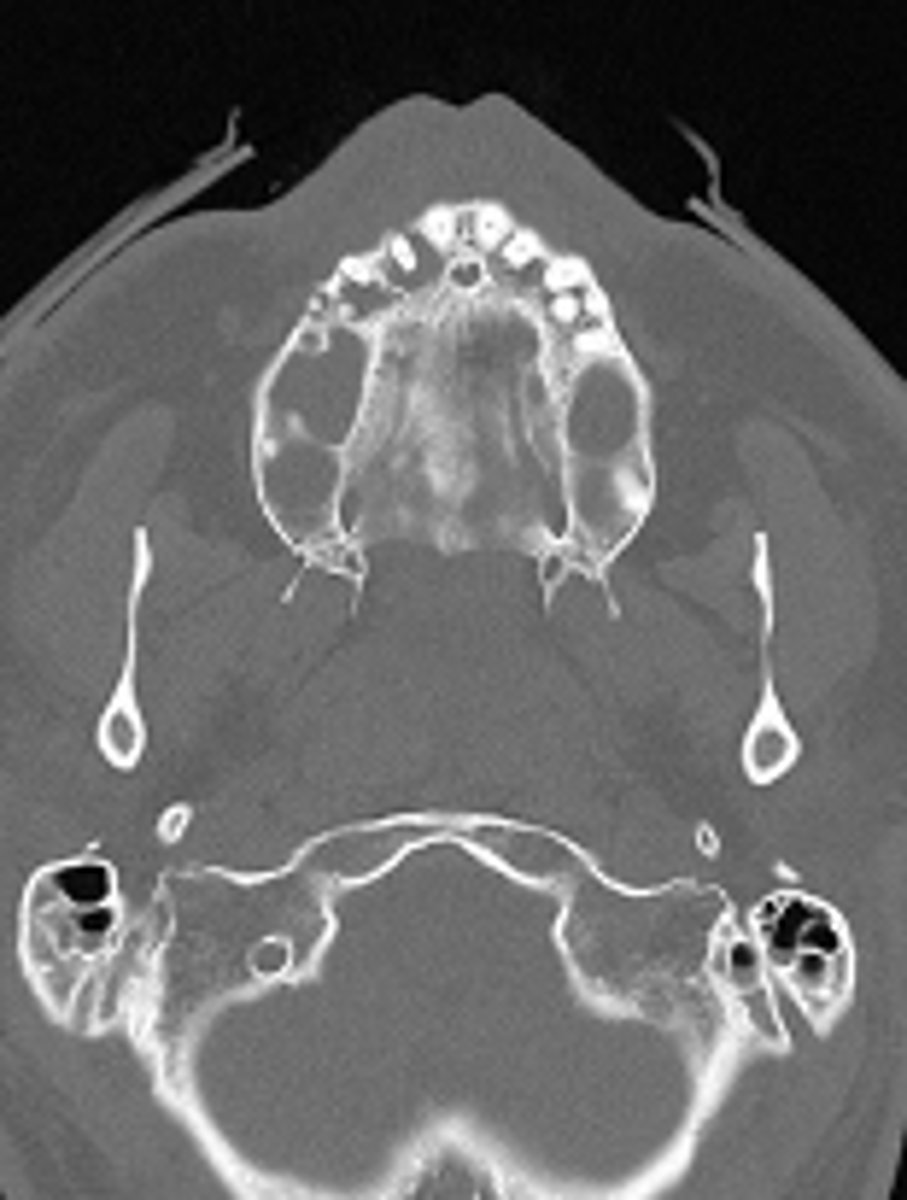

axial plane

ID the CT view: